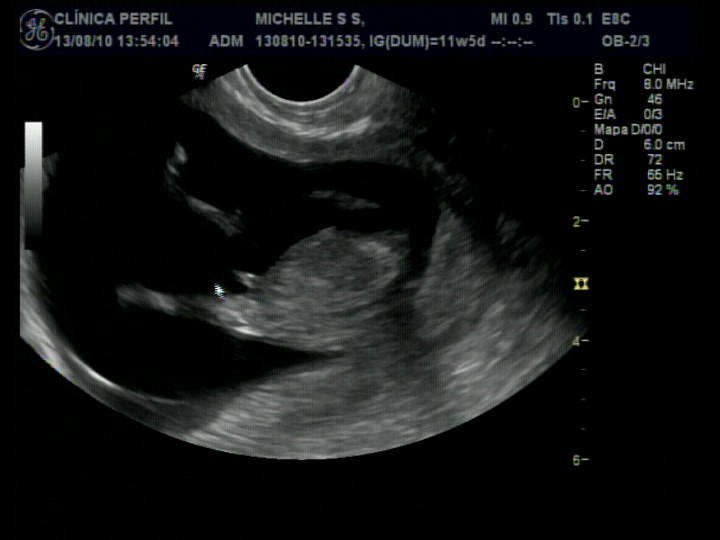

2ª Ecografia - Transnucal - 13/08/2010

Estão vendo?? Não sou mais um grãozinho de feijão!!!

Chupando dedinho?!!

Olha minhas perninhas cruzadas !!!

Mamãe tá achando q sou um homenzinho! Mas o médico não confirmou nada!

Por esse exame existe uma grande probabilidade de se detectar algumas doenças, mal formações e doenças congênitas. Por exemplo: A síndrome de down.

Mas o médico disse que o exame está normal! Graças à Deus!